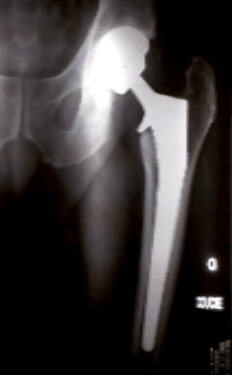

L’objectif de cette intervention est de remplacer l’articulation coxo-fémorale (articulation entre le bassin et la partie supérieure du fémur) par une articulation en métal plastique ou céramique.

Elle se compose d’une cupule métallique (titane ou inox) mise en place dans le bassin et d’une tige mise en place dans le fémur, et d’une interface qui reconstruit l’articulation proprement dite que l’on appelle le couple de frottement. Ce dernier peut être une articulation céramique – céramique, métal-polyéthylène ou céramique-polyéthylène selon les cas.

La tige et la cupule sont actuellement revêtues d’un revêtement spécifique à base de poudre d’os (hydroxy- apatite) qui permet une fixation biologique sans ciment avec de bons résultats à moyen et à long terme. D’après une étude réalisée récemment la survie de la tige utilisée est de 93% à 30 ans ce qui signifie que 93% des prothèses sont encore en place 30 ans après leur pose.